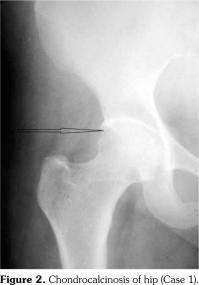

On examination, there was swelling and painful restriction of movement in her right knee. Imaging revealed calcification of cartilage of wrists, knee joints and hip joints although no microscopic confirmation was possible at this stage (Figure 1-4). She was investigated for a possible cause for CC, although investigations to screen for a metabolic cause turned out to be negative with a possibility for hereditary CC.